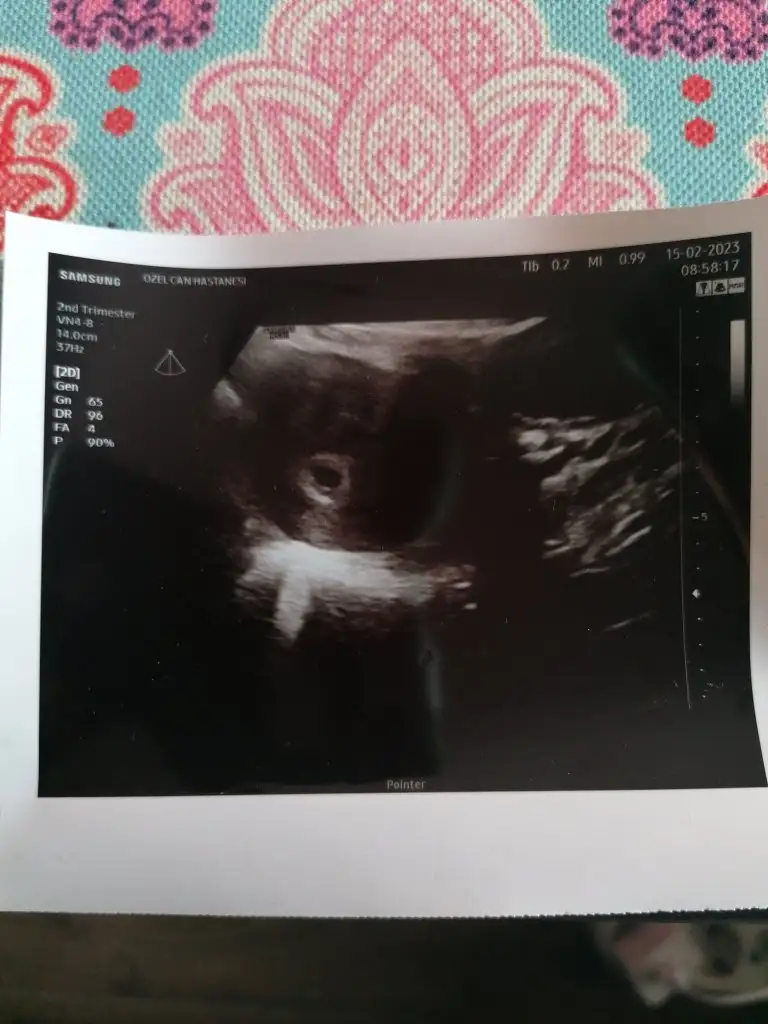

• IMG_20230215153828323.webp

IMG_20230215153828323.webp

33,4 KB · Görüntüleme: 77